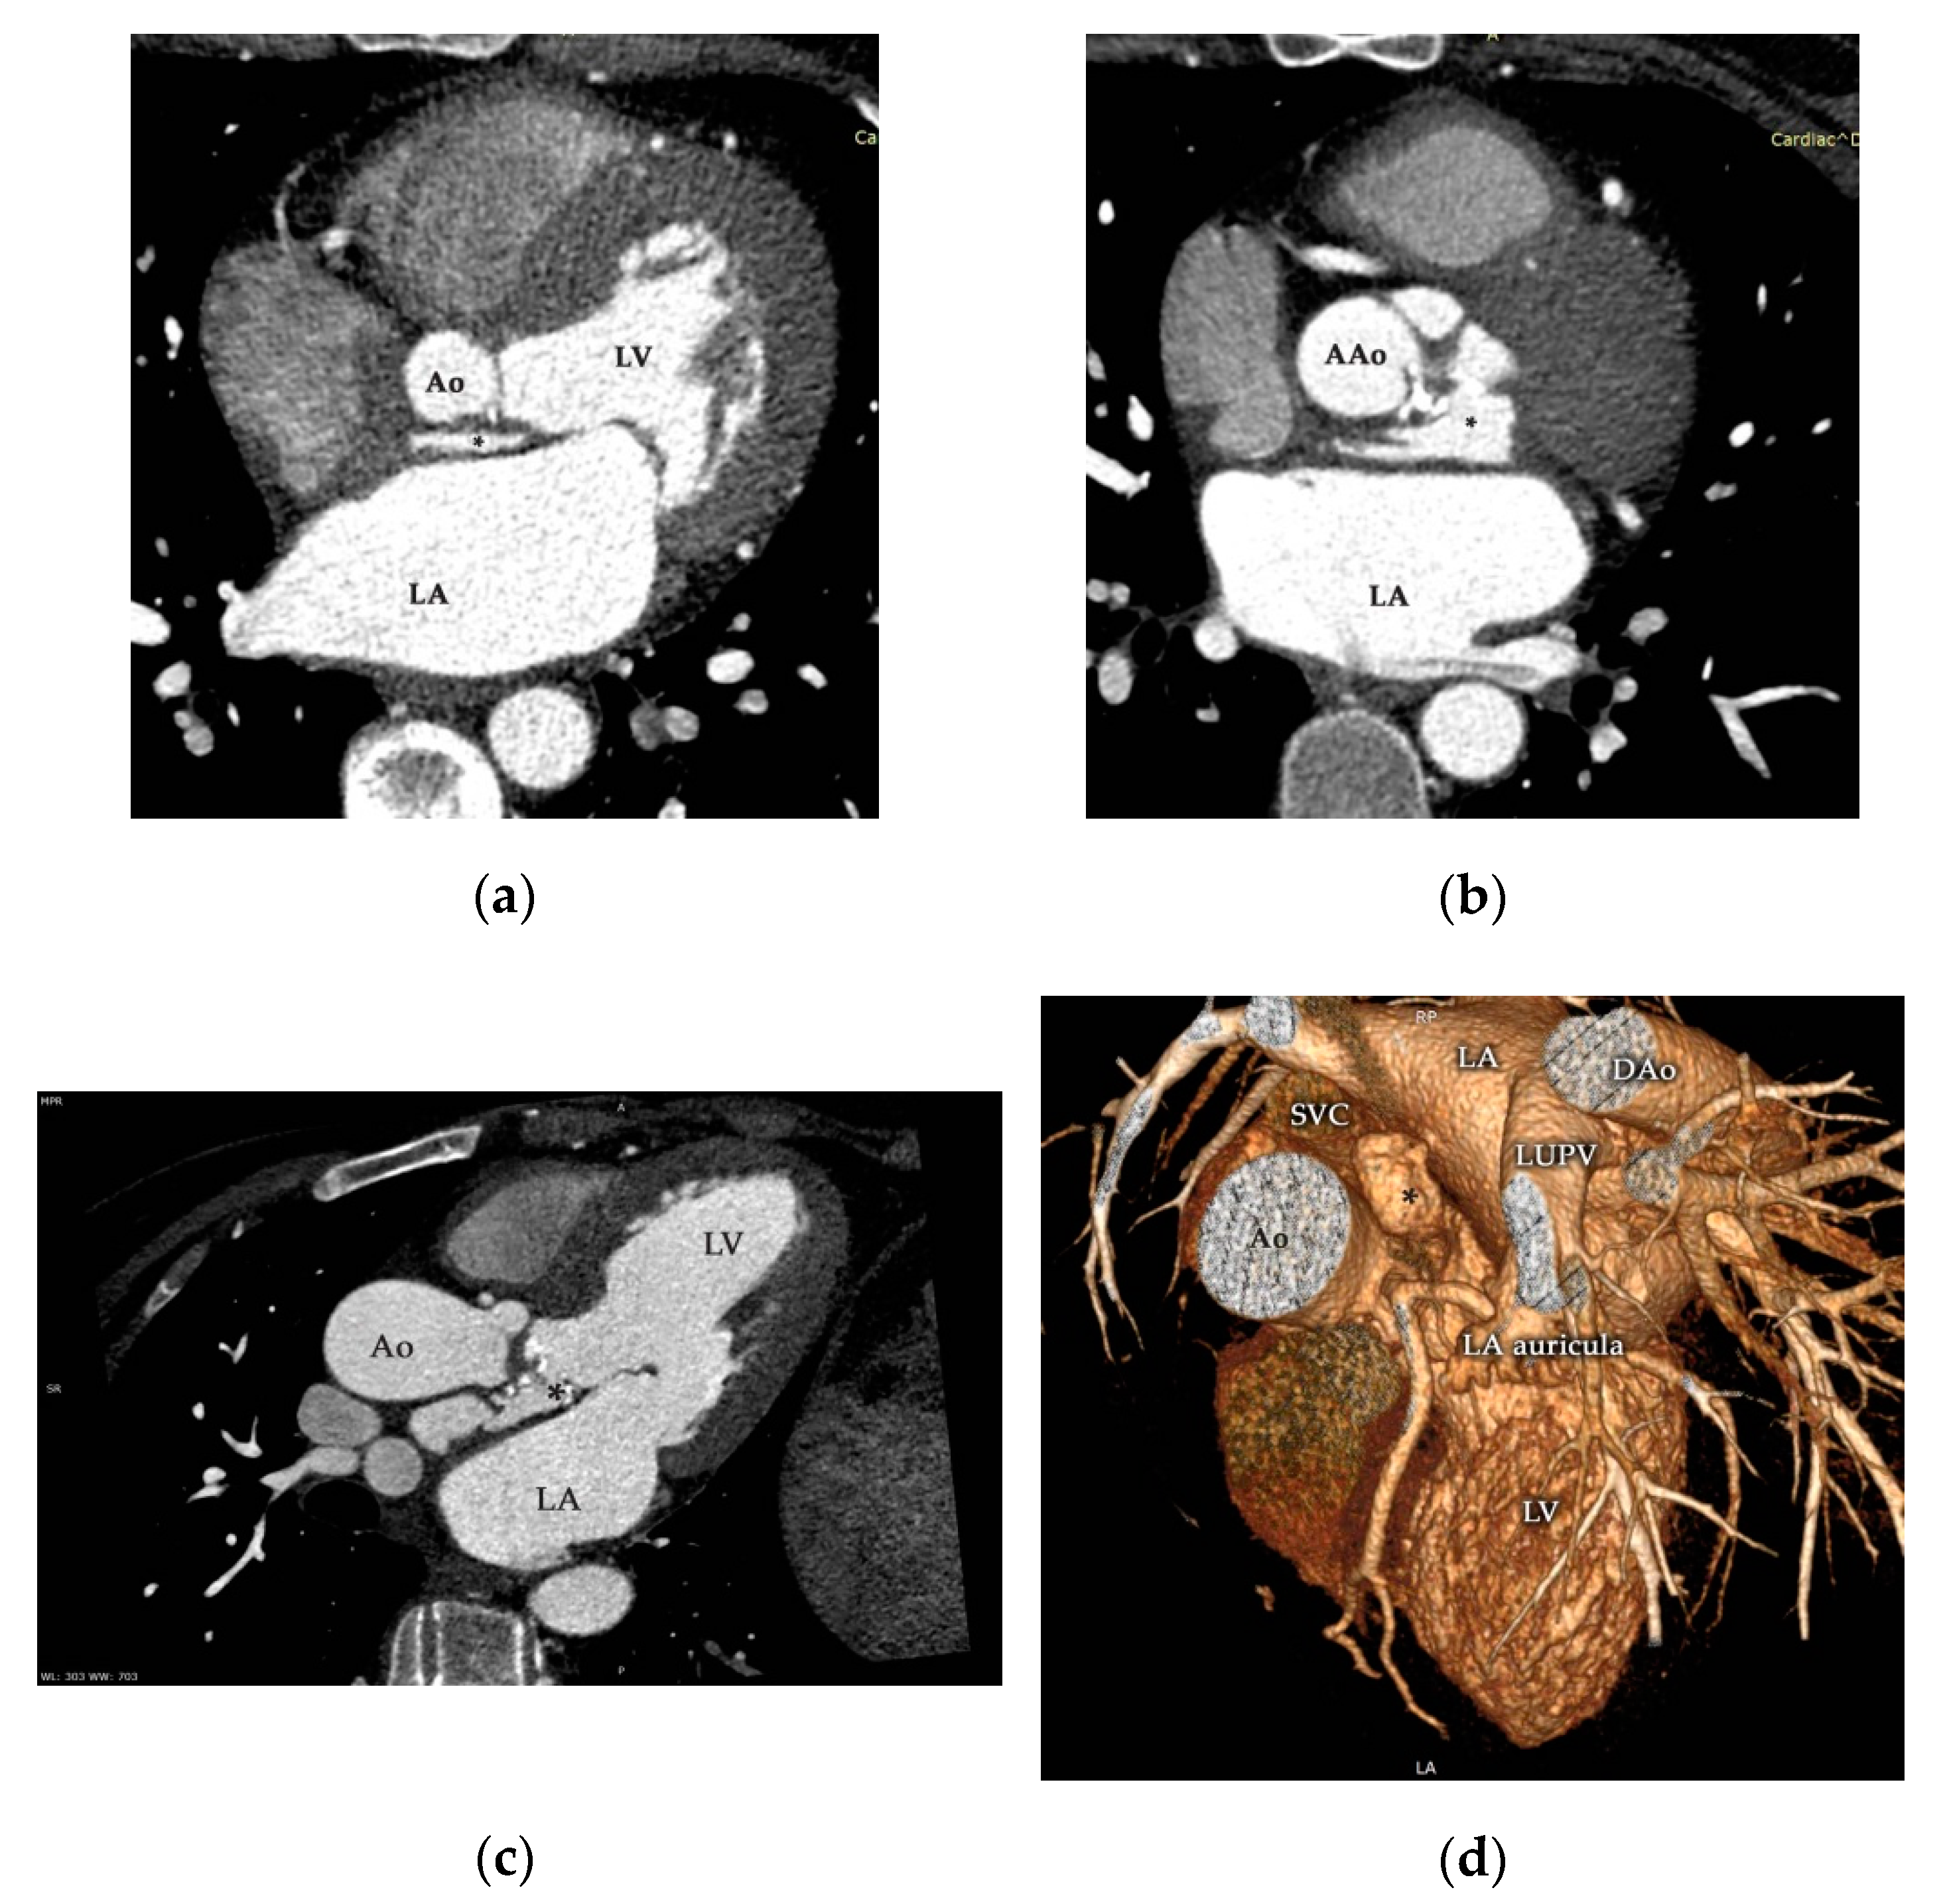

2. Case Presentation